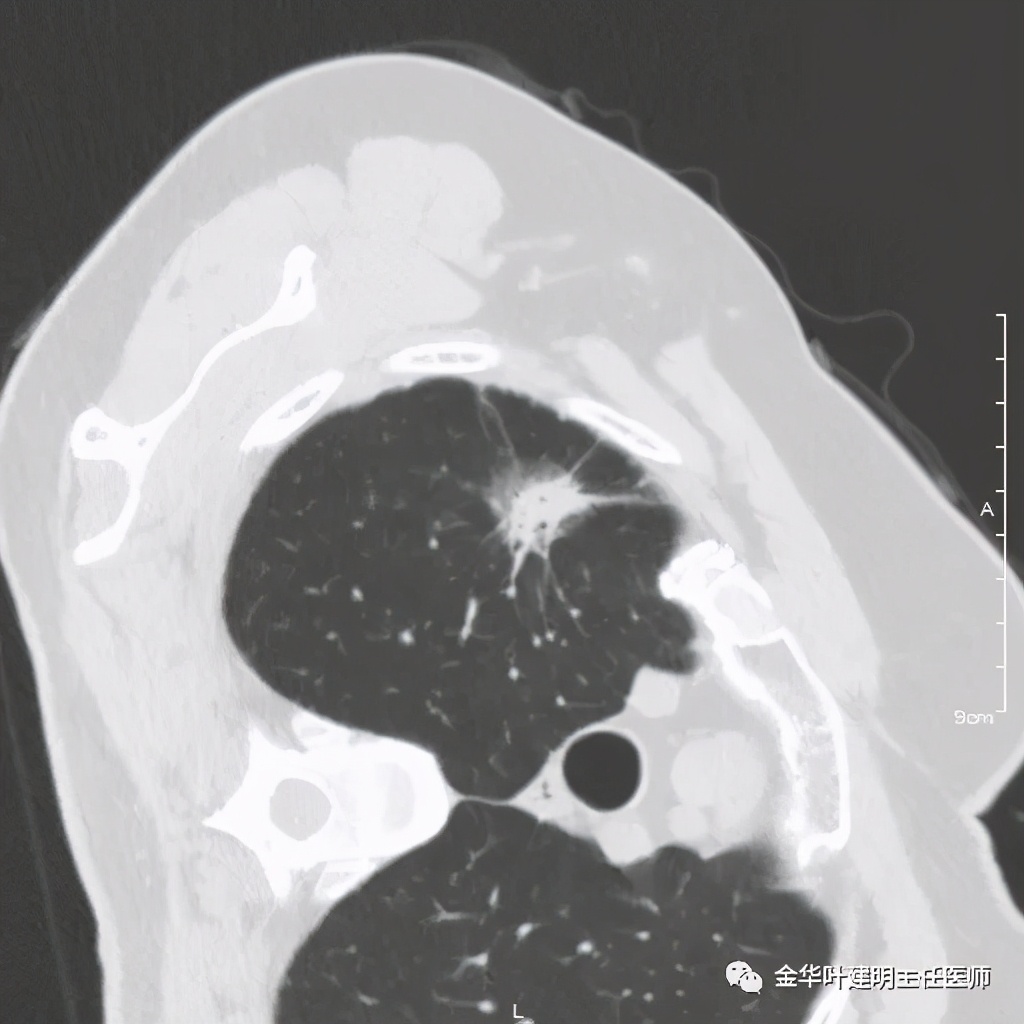

六、神经内分泌癌(此例为不典型类癌,小细胞癌以后再总结):

影像特征:不典型类癌一般圆形生长,实性,边缘比较光滑,但硬度不够。侵蚀力也不够。就像这例,我们发现其与肺动脉接触的地方,居然无法推压血管,反而肿瘤被血管占据了其生长的位置,在支气管内,肿瘤也是对支气管壁没有造成明显的破坏。也就是说 圆形边清较软、侵蚀力弱的实性结节 要考虑类癌的可能性。